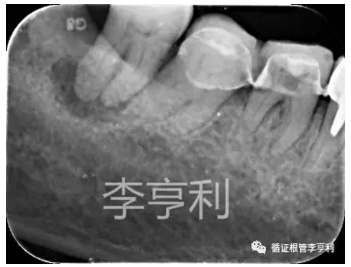

【轉診原因】:46器械分離

【病史】:46活髓牙,行冠修復后逐漸出現冷熱刺激痛及自發(fā)痛,轉診醫(yī)生診斷該牙為不可逆性牙髓炎,并開始根管治療。在疏通MB根的途中,發(fā)現#15 K 銼分離致根管無法疏通,隨后轉至我處

【輔助檢查】:遠中角度投射根尖片,見斷械影像移向近中,故判斷器械分離于近中頰根,根尖周未見明顯異常 (詳見CBCT┃如何使用傳統(tǒng)根尖片)